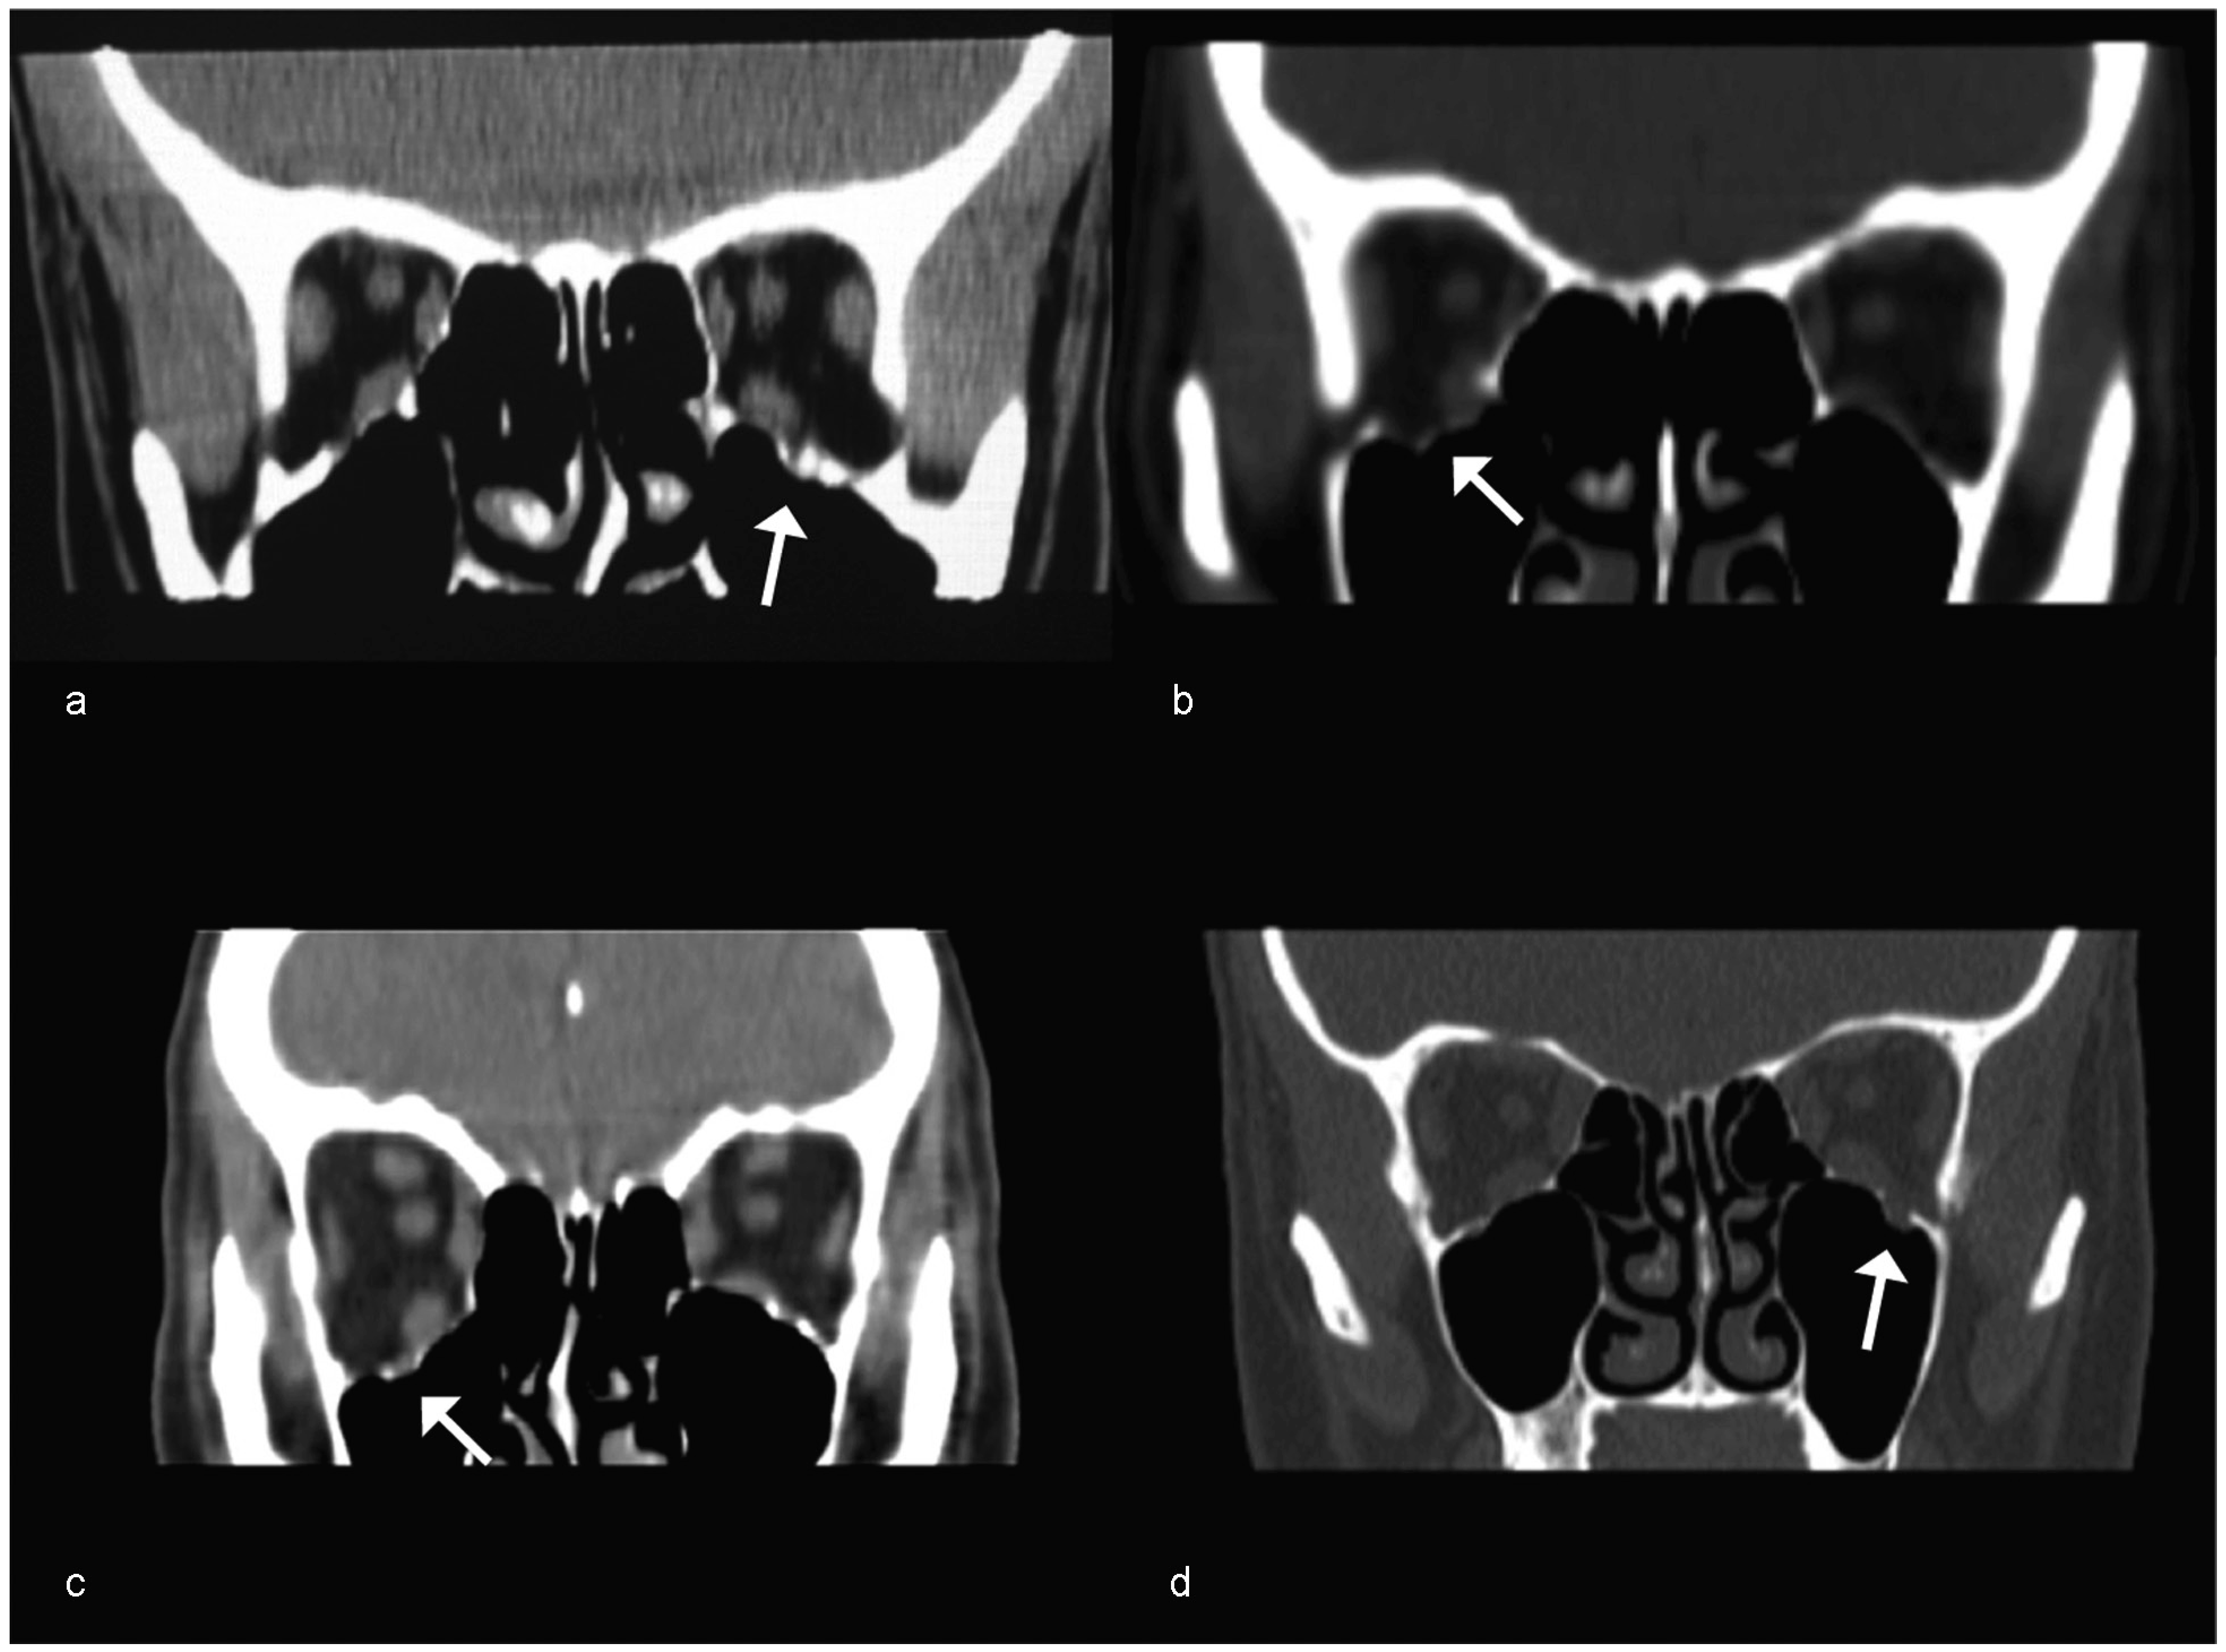

Case 1